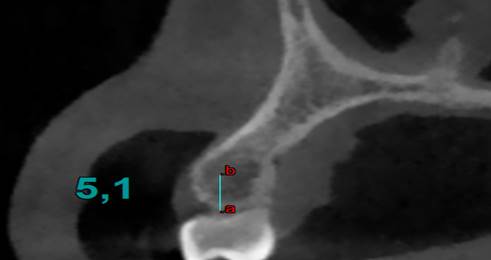

§ Por cada corte se tomaba en cuenta 0.5 mm desde la cresta alveolar hacia la zona de la línea mucogingival. (imagen 1)

§ Con una profundidad de 0.6 mm a través de la cortical hacia la tabla ósea que es el valor mínimo de un microtornillo ortodóntico en sentido horizontal (imagen 2) interradicular. Las Zonas a medir fueron:

Finalmente se mide las Unidades Hounsfield (UH) a 6 mm intraóseo e interradicular. (Imagen 1,2,3,4).